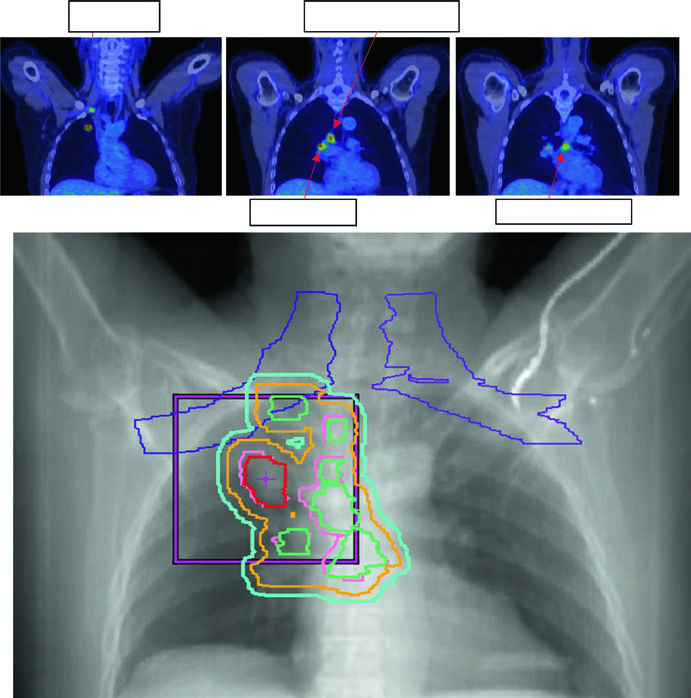

CPNPC localmente avançado (estádios II-III): controle nodal e integração com quimioterapia

No estádio localmente avançado, a expansão iGTV → iCTV aumenta para 0,5 a 0,8 cm, reflexo dos dados histológicos que mostram extensão microscópica significativa no CPNPC. A margem PTV depende do nível de controle de movimento e IGRT implementado:

- 1,0–1,5 cm sem controle de movimento/IGRT

- 0,5–1,0 cm com TC 4D ou CBCT, mas não ambos

- 0,3–0,5 cm com TC 4D + kV/CBCT (abordagem preferida)

A dose padrão para CPNPC estádio II-III com quimioterapia concomitante é 60 Gy em 30 frações (2 Gy/fx). Doses de escalada acima de 60 Gy não demonstraram benefício em ensaios randomizados e aumentaram toxicidade. O GTV inclui tumor primário e linfonodos acometidos visíveis em TC ou PET.

A Figura 13.3 do texto ilustra um caso cT1cN3M0 IIIB: tumor no LSD com linfonodo hilar direito, subcarinal, paratraqueal e SCV direita acometidos. O plano de 60 Gy/30fx cobre todos os sítios PET-positivos com exclusão das cadeias eletivas contralaterais. A Figura 13.4 mostra um caso cT4N3M0 IIIC com SCV bilateral comprometida e síndrome de veia cava superior, exigindo campo que inclui mediastino superior bilateral.